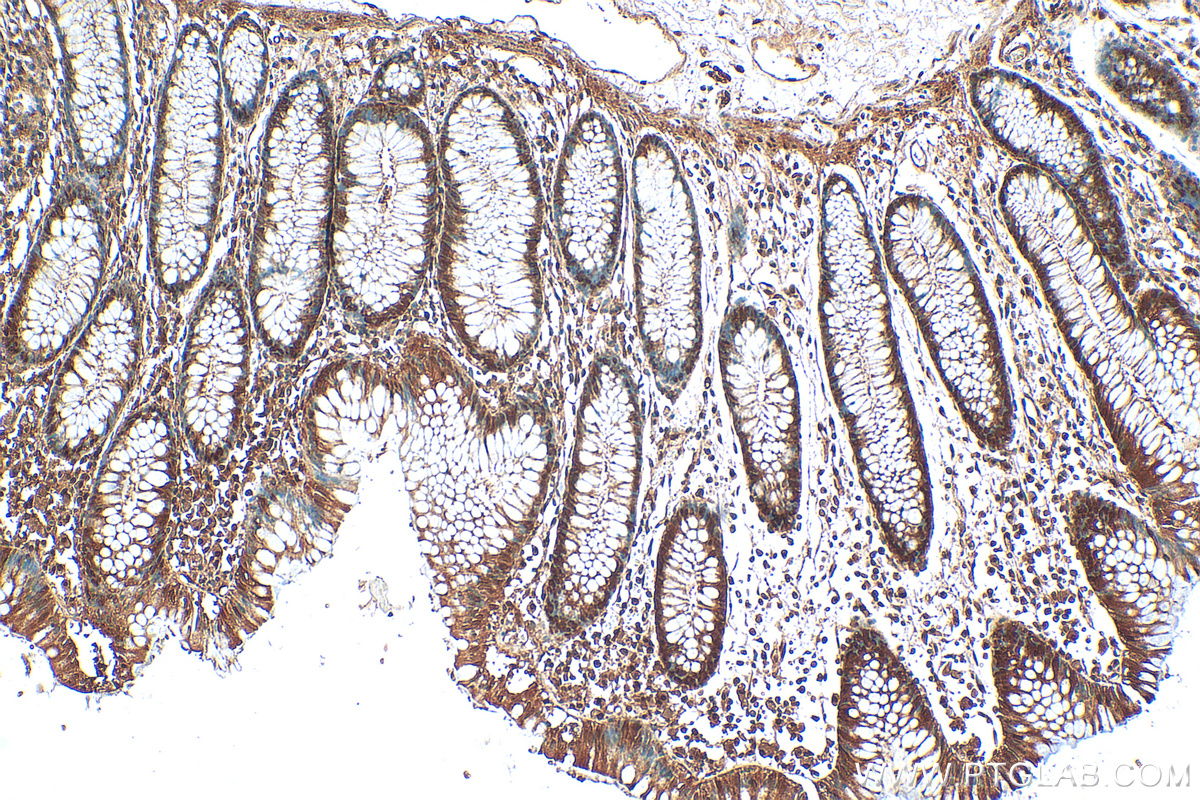

| Positive IHC detected in | human colon tissue, human kidney tissue Note: suggested antigen retrieval with TE buffer pH 9.0; (*) Alternatively, antigen retrieval may be performed with citrate buffer pH 6.0 |

| Immunohistochemistry (IHC) | IHC : 1:50-1:500 |